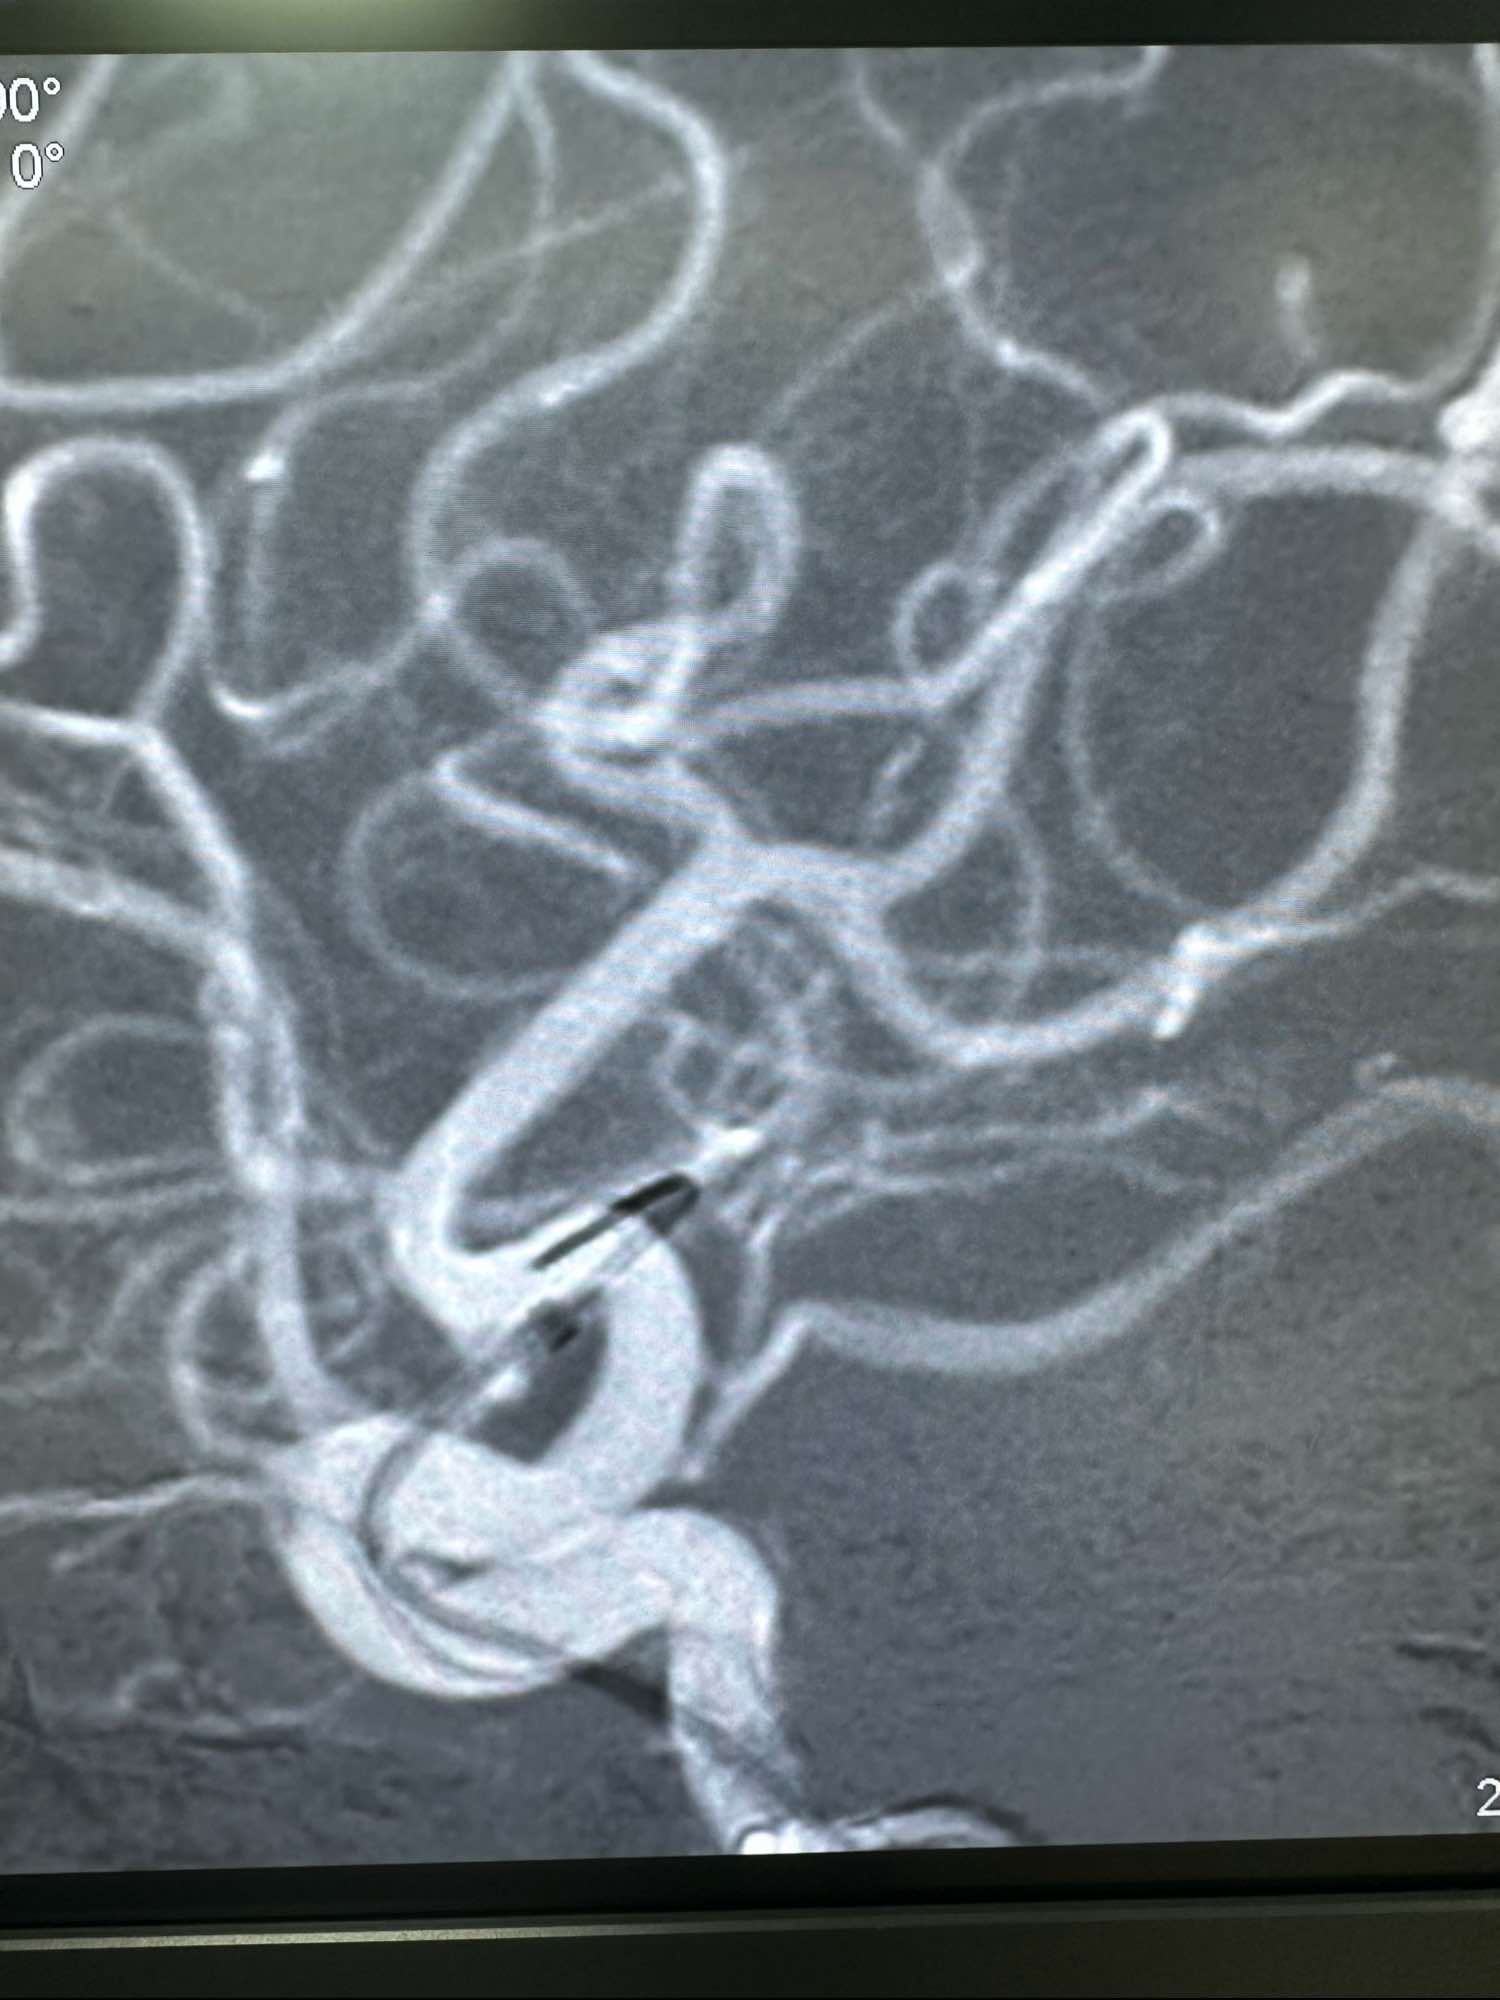

术前的3D

另外一个角度